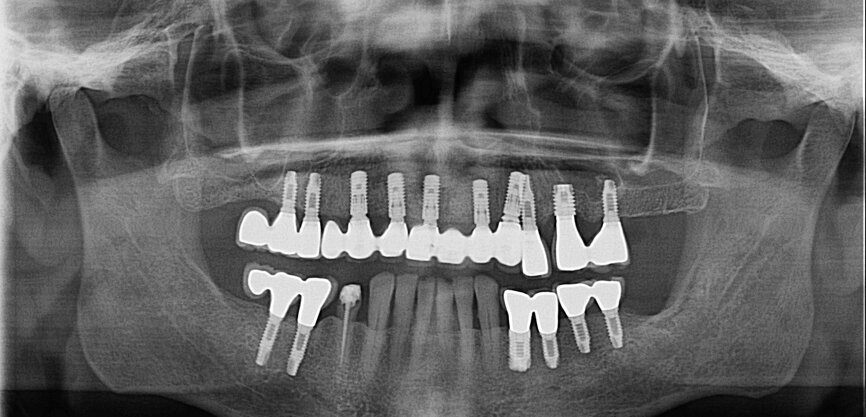

Fig. 11: Post-op dental panoramic tomogram.

Fig. 12: Screwed on superstructure.

The first was a 51-year-old patient who smoked 30 cigarettes per day and suffered from diabetes and stress (Figs. 1–8). The second was a 76-year-old male patient in good physical condition who smoked 40 cigarettes per day. He underwent reconstruction of the premaxilla (Figs. 9–13). The third was a healthy female patient of 24 years of age who smoked 20 cigarettes per day. She required a sinus lift in region #25 (Figs. 14–21). The patients were informed of the intended process in detail and signed the surgical protocol containing information concerning possible risks of failure and complications, as well as information on the alloplastic and synthetic materials to be used.

Digital radiographic images were taken at the time of surgery, 24 hours postoperatively and one month later in order to evaluate implant success (Figs. 6, 7, 11, 13, 15 & 20). In none of the patients inflammatory processes were found and all implants remained stable.